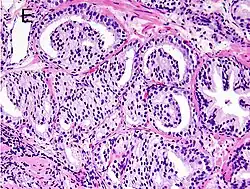

Gleason 4

Gleason pattern 4 glands are no longer single/separated glands like those seen in patterns 1–3. They look fused together, difficult to distinguish, with rare lumen formation vs Gleason 1–3 which usually all have open lumens (spaces) within the glands, or can be cribriform-(resembling the cribriform plate/similar to a sieve: an item with many perforations). Fused glands are chains, nests, or groups of glands that are no longer entirely separated by stroma-(connective tissue that normally separates individual glands in this case). Fused glands contain occasional stroma giving the appearance of "partial" separation of the glands. Due to this partial separation, fused glands sometimes have a scalloped (think looking at a slice of bread with bite taken out of it) appearance at their edges.[4][7]

-

Gleason score 6 (3+3) -

Cribriform pattern: Gleason grade 4 -

Gleason score 7 (3+4) with minor component of cribriform glands -

Gleason score 8 (4+4) with glomeruloid glands -

Gleason score 8 (4+4) with irregular cribriform glands -

Gleason score 8 (4+4) with fused glands with cytoplasmic vacuoles -

Gleason score 8 (4+4) with poorly-formed glands -

Gleason score 9 (4+5) with cribriform glands, some with necrosis -

Gleason score 10 (5+5) with cords of cells -

Gleason score 10 (5+5) with individual cells -

Gleason score 10 (5+5) with solid sheets of cells